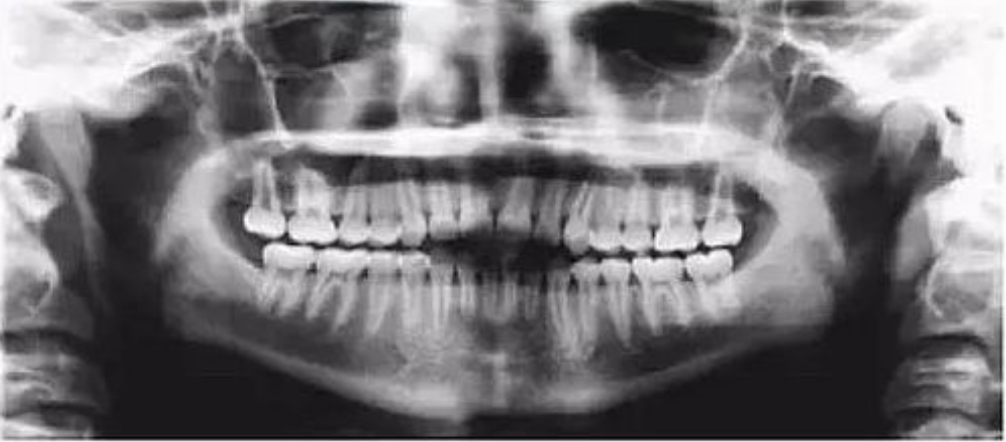

二、影像辐射穿透度不够,前牙显示较大

【失误原因】

定位聚焦激光束或自动对焦(Autofocus)激光束定位过靠前。

【解决方法】

将定位聚焦光束后移至侧切牙根尖位置。